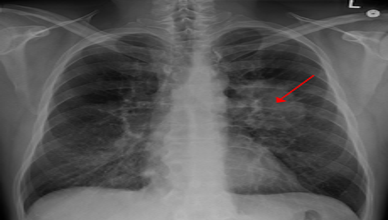

A questão do Rn é tão preocupante que esse gás é responsável por 10 a 15% de casos de câncer de pulmão no mundo. Dados da Organização Mundial da Saúde registra que ao somar com os casos de câncer de pulmão causado pelo cigarro, o número de caso sobe para 25%.